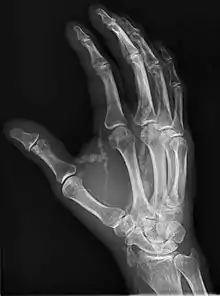

Hand radiograph showing tumoral calcinosis, PA radiograph of the right hand showing tumoral calcinosis-like metastatic calcification in a patient on dialysis. Dialysis alters calcium phosphate product (>70). Idiopathic tumoral calcinosis is autosomal dominant and is not associated with dialysis. Note the premature arterial calcification which is a clue that this is a renal patient. Vascular calcification contributes to an increase in morbidity.

Tumoral calcinosis is a rare condition in which there is calcium deposition in the soft tissue in periarticular location, around joints, outside the joint capsule.[1] They are frequently (0.5–3%) seen in patients undergoing renal dialysis. Clinically also known as hyperphosphatemic familial tumoral calcinosis (HFTC), is often caused by genetic mutations in genes that regulate phosphate physiology in the body (leading to too much phosphate (hyperphosphatemia)). Best described genes that harbour mutations in humans are FGF-23,[2] Klotho (KL),[3] or GALNT3.[4] A zebrafish animal model with reduced GALNT3 expression also showed HFTC-like phenotype,[5] indicating an evolutionary conserved mechanism that is involved in developing tumoral calcinosis.

The name indicates calcinosis (calcium deposition) which resembles tumor (like a new growth). They are not true neoplasms – they don't have dividing cells. They are just deposition of inorganic calcium with serum exudate. Children and adolescents (6 to 25 years) are the most commonly affected. The symptom that the accumulations cause is not pain but swelling around joints. They have propensity to enlarge progressively and ulcerate the overlying skin and extrude. They are most common around shoulders, hips and elbows. Laboratory evaluation reveal normal serum calcium levels and hyperphosphatemia. Rarely ALP (alkaline phosphatase – an enzyme active at sites of bone formation) may be elevated. Treatment is normalization of serum phosphate levels and resection of lesions. Surgical removal should be complete and if part of it is left, recurrence is likely to occur. Cutting through the excised calcium deposition reveals semifluid calcium suspension in albumin encapsulated by fibrous tissue.